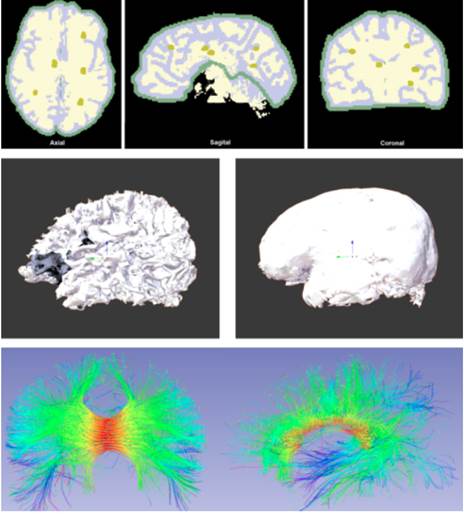

Se crearon dos escenarios de entrenamiento, uno basado en imágenes craneales y otro para imágenes abdominales. A través de 3D Slicer y con las imágenes RMI, se obtuvo un modelo 3D del cerebro segmentando en estructuras muy específicas como materia gris, materia blanca y cuerpo calloso. Se incluyeron objetos virtuales que representan tractos neurológicos diferenciados por diversos colores, con el fin de mostrar estructuras que no son fácilmente visibles en el desarrollo de una intervención quirúrgica. Se crearon cinco tumores ficticios en zonas aleatorias del cerebro, con el fin de desarrollar una prueba de validación del prototipo de realidad mixta. Para la obtención de materia gris, materia blanca y tumores como objetos 3D, se hizo la segmentación de dichas zonas correspondientes a la parte central de cada corte del cerebro (axial, sagital y coronal) y posteriormente con el proceso de segmentación realizado se crearon las partes en un modelo 3D como se muestra en la Fig. 2.